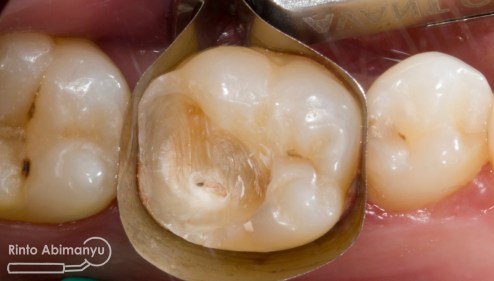

Setelah saya liat keadaan klinisnya ini yang saya lihat…

Gigi 46 terlihat kavitas masih ada karies yang sangat luas dan ada spot sudah terjadi tembus ke kamar pulpa.